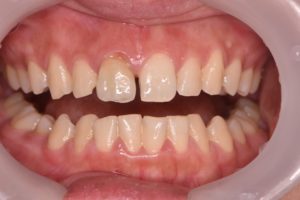

詳細:前肢の審美障害を主訴に来院された患者さんです。上の前歯に過去に治療し不適合となったクラウンが入っており、その横の歯に欠けた跡がみられました。不適合のクラウンのみをやりかえると左右中切歯の幅がかなり差が生じてしまうことから、欠けている部分をダイレクトボンディングにて形態修正を行い、不適合クラウンはジルコニアセラミックで再治療することで審美障害を改善しました。

黄色:ダイレクトボンディング

オレンジ:ジルコニアセラミッククラウン